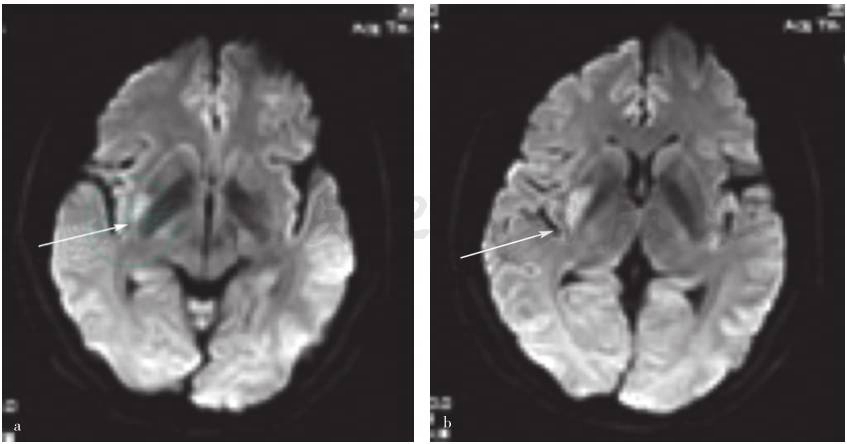

实验室检查血、尿、粪便常规、肝肾功能、血脂、C反应蛋白、红细胞沉降率、甲状腺功能及血清同型半胱氨酸均于正常值范围;血清抗可提取性核抗原(ENA)、抗中性粒细胞胞质抗体(ANCA)、自身抗体及抗核抗体均呈阴性反应。心脏彩色超声扫描、动态心电监测均未见异常变化。颈部血管彩色超声显示双侧颈动脉粥样硬化表现,左侧伴多发硬化斑块形成。入院当日头部弥散加权成像(DWI)扫描显示,右侧基底节区新发脑梗死(图1)。头部MRA检查未见明显异常(图2);高分辨率磁共振大脑中动脉粥样硬化斑块分析显示,左侧大脑中动脉起始段下壁小斑块,右侧大脑中动脉M1段近分叉部前壁可疑小斑块(图2)。

图1 患者头部MRI的DWI序列

a、b.均显示右侧基底节区新发脑梗死(箭头所示)